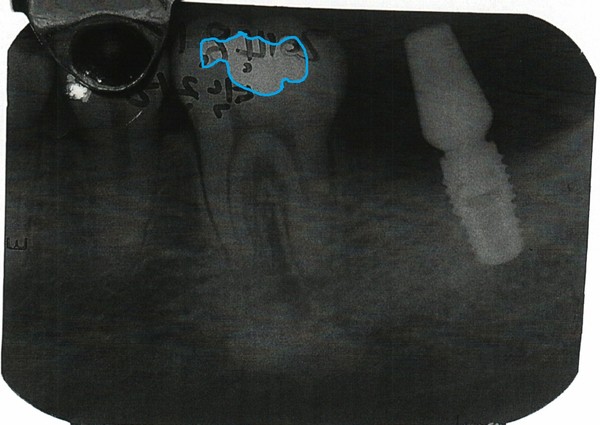

- ▲ 치과의사 문씨가 주신씨를 치료한 증거로 검찰에 제출한 치근단 엑스레이 속 36번 치아의 아말감 형태. ⓒ 김우현 원장 제공

<인>: 박주신씨 명의의 치근단 엑스레이와 자생병원의 구외 엑스레이에 대해 어떤 차이점이 있는지 설명을 부탁드린다.<김>: 첫 번째는 박주신 명의의 구외 엑스레이와 치근단 엑스레이를 놓고 비교했을때 36번 어금니에 치료된 아말감의 충전형태가 매우 다르게 나타난다.

구외 엑스레이의 아말감 형태는 중간부분이 오목하게 들어가는 협부(isthmus)가 명확하다. 반면, 치근단 엑스레이는 협부가 없을뿐만 아니라, 모양 자체도 다르다.

두 번째로 36번 치아형태도 치근단과 구외 엑스레이가 각각 다르게 나타난다. 치근단 엑스레이에서는 치아뿌리 상부 1/3과 중간 1/3 근원심간 너비가 비슷하다.

다시 말해, 중간부분까지는 좁아지지 않다가 치아 끝부분에 가서야 좁아지는 일반적인 양상을 띠고 있다.치근관의 만곡도 보인다.

하지만 구외 엑스레이에서는 치이뿌리 상부 1/3과 중간 1/3의 근원심간 너비차이가 현격하게 나타나, 치아뿌리 끝으로 갈수록 좁아지는 양상이다. 또 치근단 엑스레이와 달리, 치근관의 만곡이 없다.

세 번째는 36번 치아에 대한 치근단-구외 엑스레이 상에서 보이는 병소(病巢)의 유무(有無)다.

치근단 엑스레이에서는 36번 치아 아래쪽 하악골에 특발성 골경화증(idiopathic osteosclerosis)이 보이는데, 자생 구외 엑스레이는 깨끗하다. 특발성 골경화증이란 뼈의 조직이 단단히 굳어져 비정상적으로 치밀해지는 증상을 말한다.

치근단 엑스레이는 2005년 7월 촬영한 것이고 구외 엑스레이는 2011년 12월 촬영한 것인데, 골경화증이 없다가 나타났다면 모르겠으나, 있던 것이 사라지는 경우는 없다고 봐야한다.